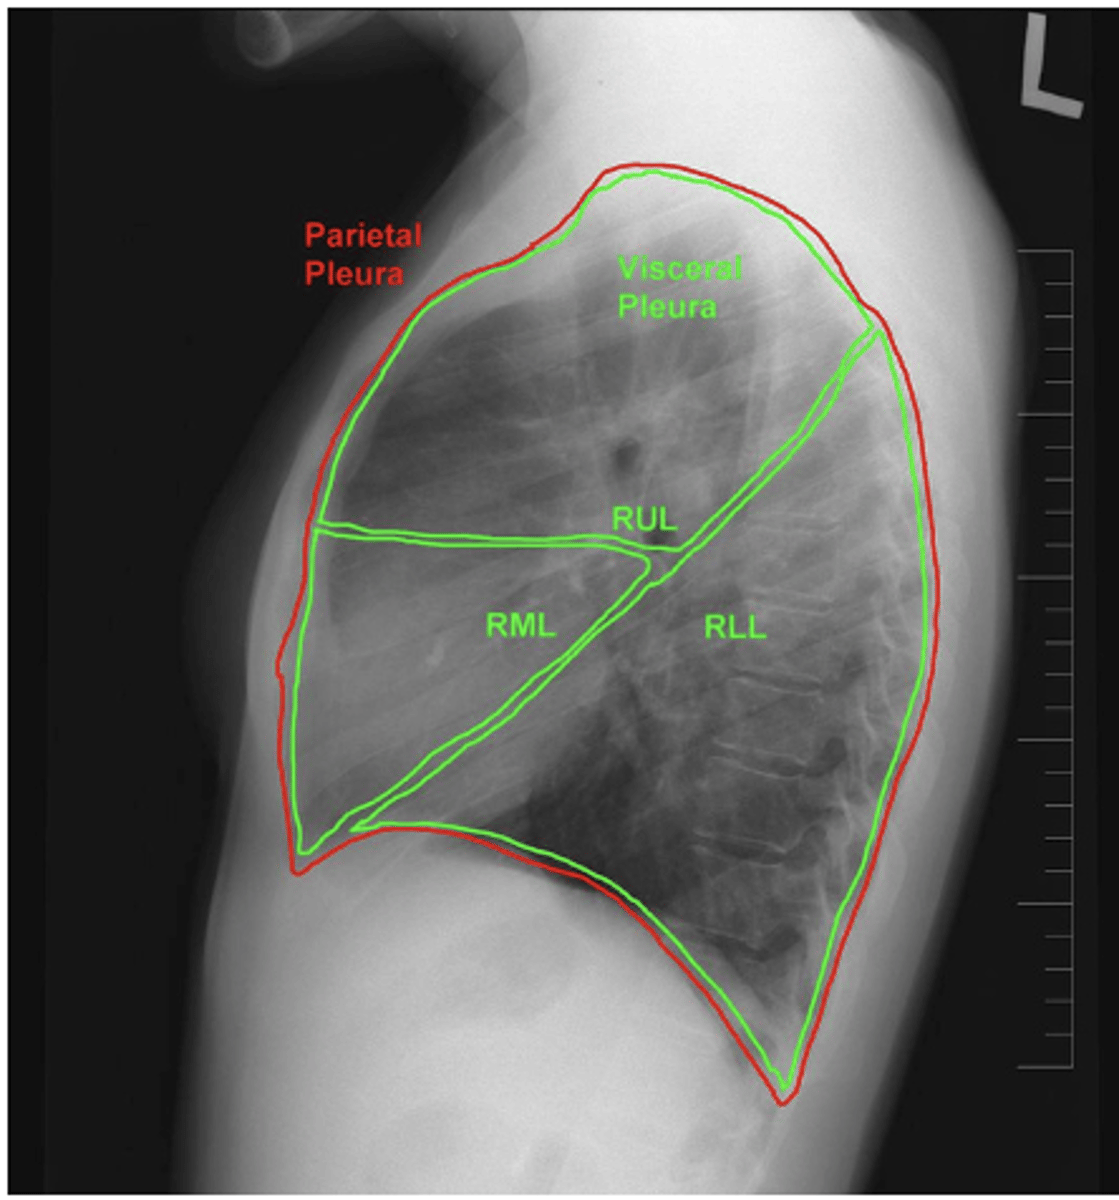

ID lobes of lungs on back of card (lateral right)

refer to picture

<p>refer to picture</p>